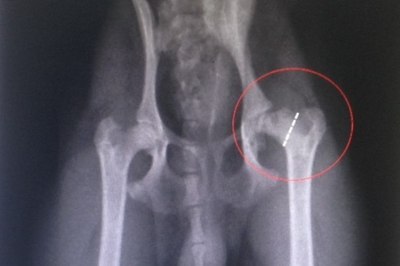

Вообщем, жил я в 2011 году в съёмной комнате, в Содрс, Ко Дублин. Уехал в этом году в в Латвию, сам, на операцию. Когда вернулся обратно, но обнаружил котёнка. Рыжего малыша. Его взял к себе мой сосед по дому, в котором я снимал комнату. Этого соседа никогда не было дома, котик никогда не был кормлен, в его ушал можно было садить картошку. Они были не вереятно грязные. В итоге это сосед съехал, забрал Кискису (так зовут кота) и через 2 недели мне перезвонил, не хочу ли я забрать кота к себе. Я не смог отказать, так как он и так у меня жил и я ему покупал еду, мыл, чесал орехи. Вот он оказался у меня. Прошло 2 месяца и он сломал бедро. Я не уверен, что он лично это сделал. Так как он до сих боиться заведённых машин, кроме моей. Я отвёл его в клинику, ренген показал что ножка - вышла из таза. Её попытались вставить и срастить, но это не дало результата. В итоге предложиди операцию : отрезать "шарик" , который вставляеться в таз. Я согласился . Хирург, он же хозяин, клиники, не взял с меня не копейки за содержания коти(до сих пор ему большая благодарность и можете расценевать как рекламу и минусить как вам угодно Ó Scanaill Veterinary Surgeons). Он сказал, я такую любовь вижу перый раз между человеком и животный. Тогда я сыкономил 60 еиро за 3 дня. Но я не знал какого друга я приобрету. Я не думал что кот способен на такое. Эта рыжая бестия ходит со мной в магаз и ждёт меня около него и идёт обратно. Лучше собаки. Потом я специально искал отдельное жильё, чтобы ему был свободный доступ на улицу. И в итоге нашёл. Хотя меня хирург, который делал ему операцию предлагал за одно " отрубить " ему орехи. Я не смог, ему и так дасталось, как мне показалось.